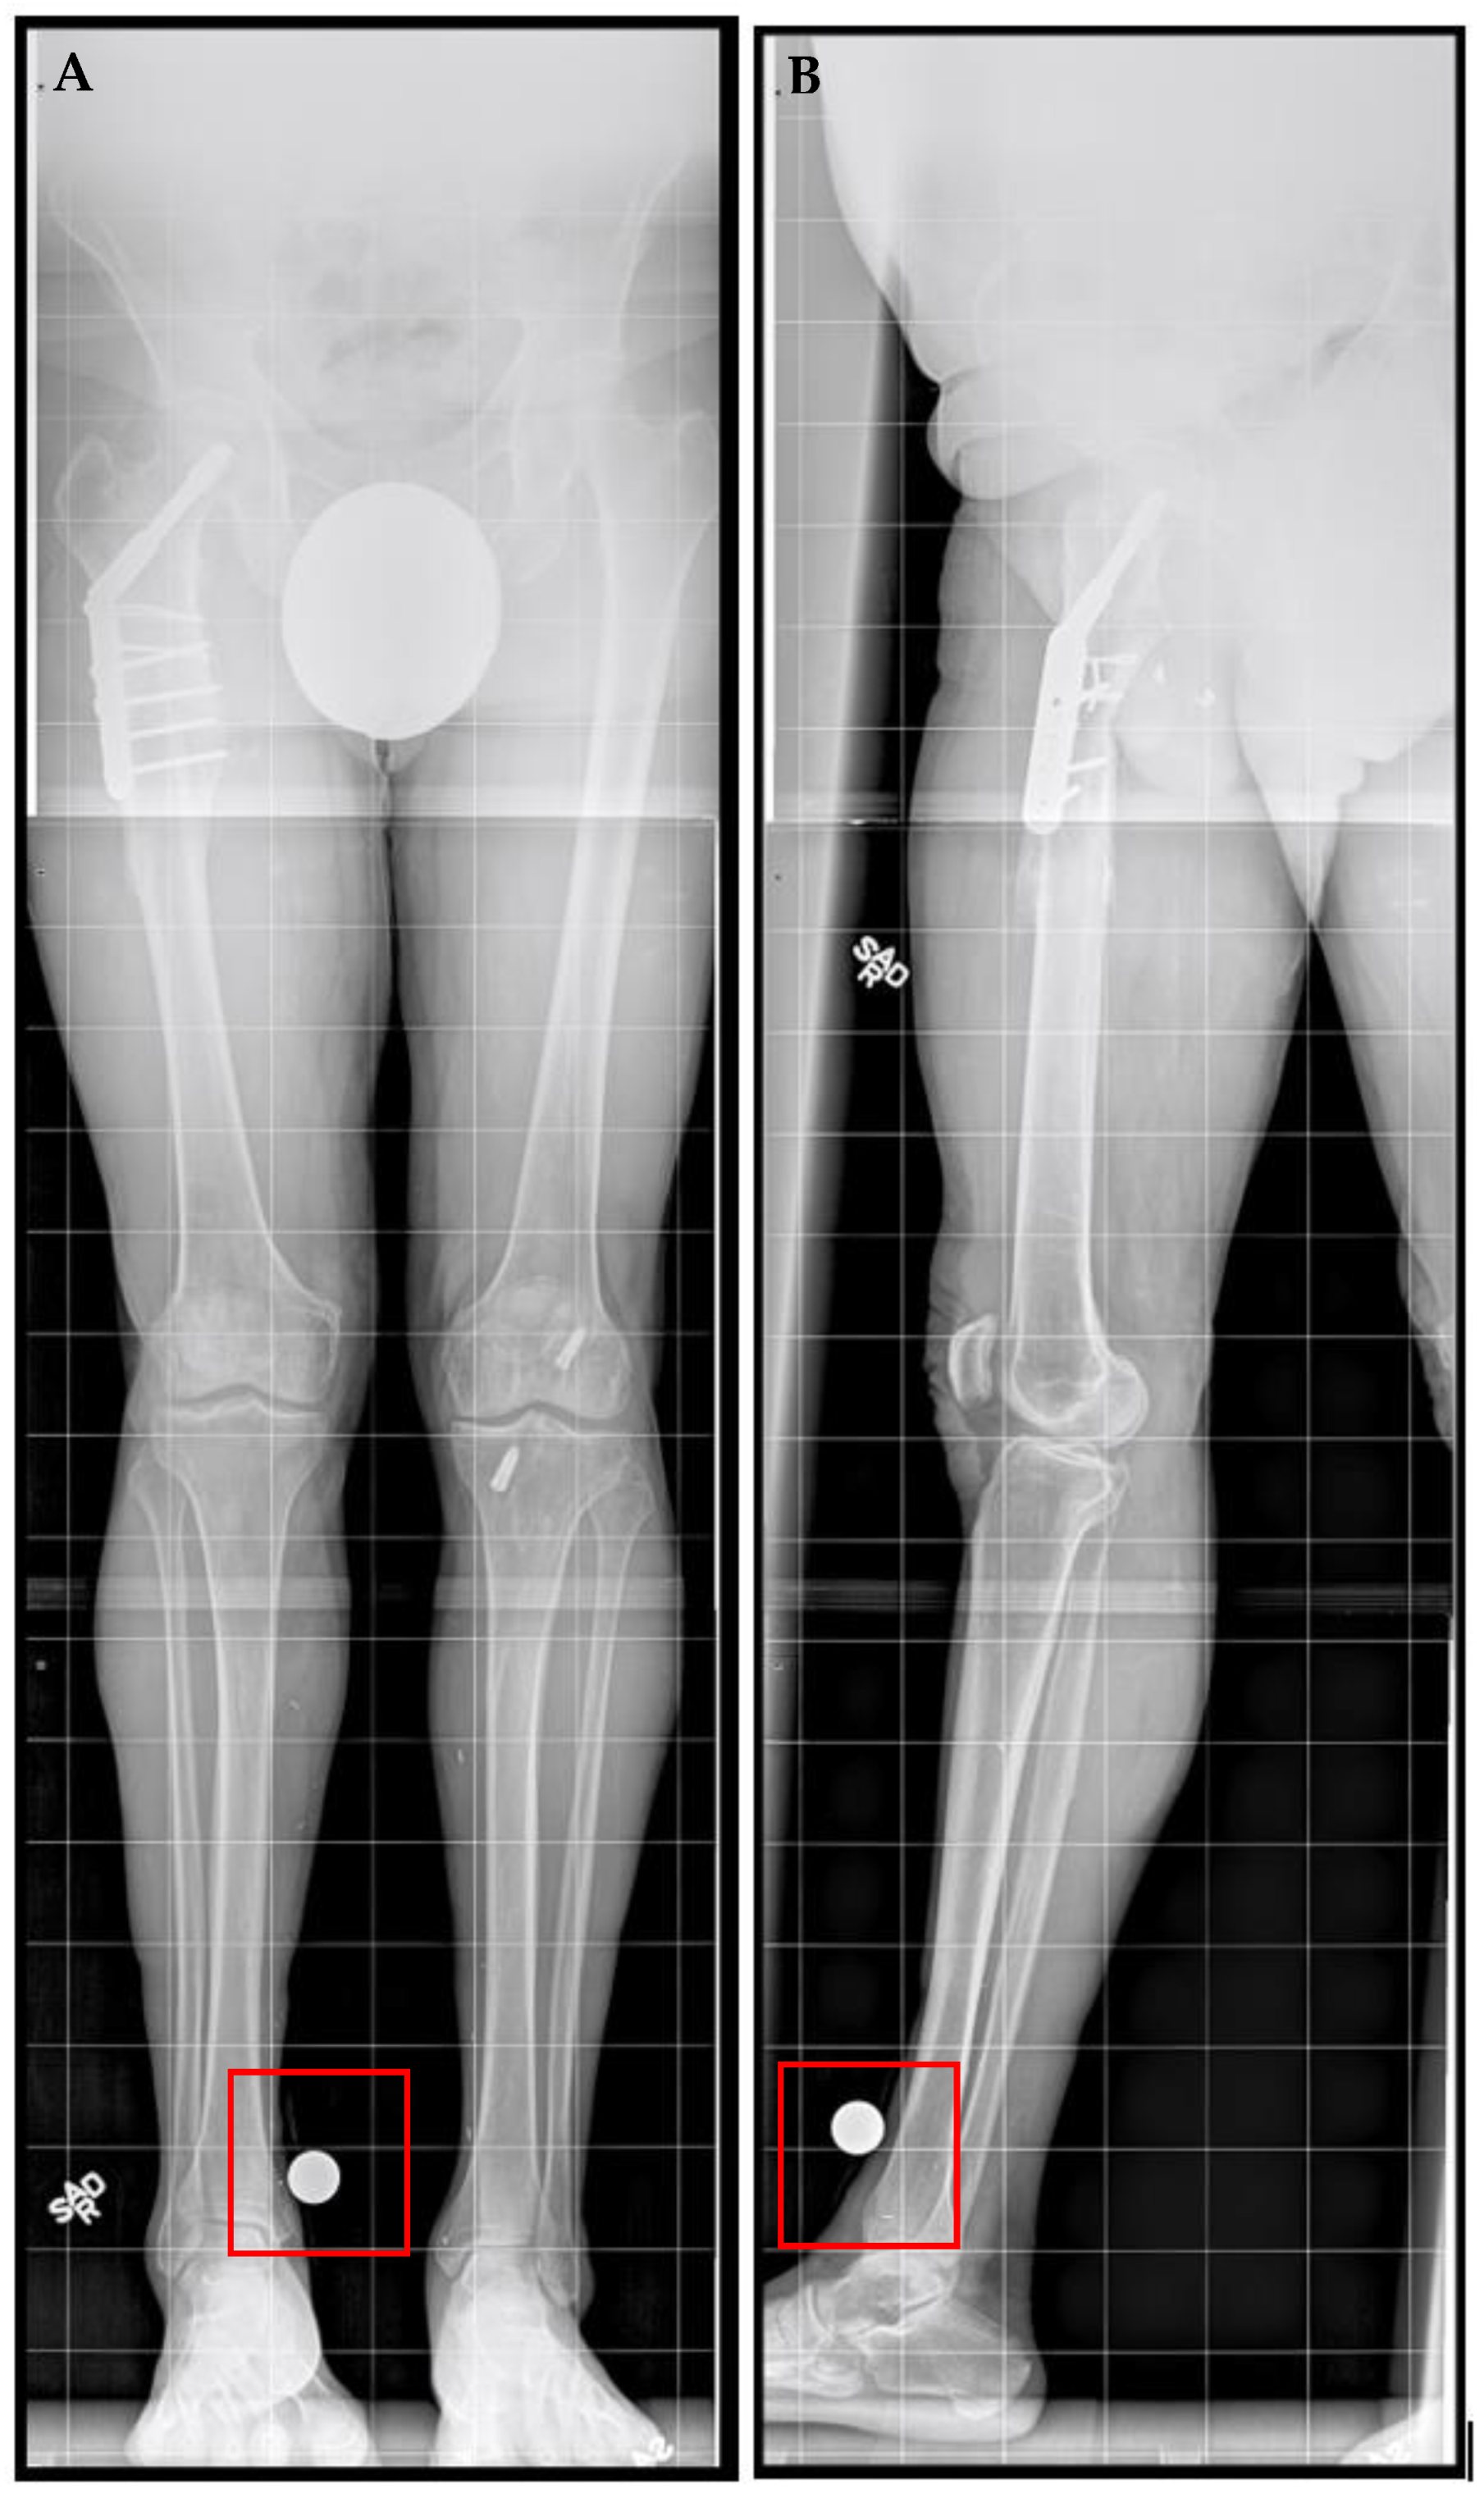

A 71-year-old male, an avid skier and cyclist with a history of sports-related injuries, was referred for LLD. He suffered a right femur fracture at age 53 that required femoral IM nail fixation. He also experienced a right intertrochanteric femur fracture at age 67, for which he underwent sliding screw fixation. He walked with a half-inch heel lift inside his right shoe. He had been experiencing lower back and right knee pain for more than three years prior to initial presentation. He stated that he did not want to wear shoe lifts for the rest of his life and found it difficult to maintain an active lifestyle. The patient also had a history of prostate cancer and coronary artery bypass surgery, both of which had been treated successfully. He no longer experienced cardiac symptoms. Upon physical examination, he demonstrated right femoral retroversion with a slight pelvic tilt with compensation noted. There was a femoral discrepancy (right side shorter than left) of approximately 2 cm when performing the Galeazzi test. Radiographs showed mild osteopenia with plate and screw fixation of the proximal right femur in the area of the intertrochanteric fracture, with mature bone callus formation. A 3.0 cm femoral discrepancy was measured, with the right side shorter than left side (Figure 1).

Figure 1.

Posttraumatic femoral lengthening in a 71-year-old male patient, shown preoperatively. (A) Anteroposterior bilateral long leg and (B) right long leg lateral prior to the insertion of the Precice MILN. Gray dots on the bottom represent X-ray calibration spheres.